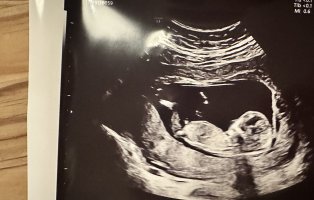

Åå, så kjedelig med dårlige bilder :/.. Jeg har dette også, men her ser man heller ikke stort. Jordmor sa ingenting om hva hun trodde eller noe som helst om kjønnet..Disse bildene var veldig dårlig til å være 14 uker. har du flere fra denne eller tidligere? burde være lett å se kjønn når man er så langt på vei. det på bilde nr 1 er ikke nub, det er en del av benet som har kommet med på bildet. Jeg tror det er jente da det ville vært veldig synlig i uke 14 om det var gutt. Ser og lang hvit strek på flere av bildene som samsvarer med jentenub.

trodde kanskje det var noe ) se hvor jeg har satt ring på bildet hihi

? Er 13+1 her